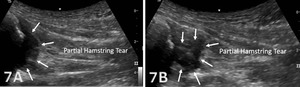

Disruption of fibrillar pattern in partial tears and ruptures. Proximally, it is important to determine if the injury is a free-tendon injury or purely a myotendinous injury.20

Early Detection of Injury / Accurate Injury Grading: MSKUS can quickly differentiate between a tendinopathy versus a strain, or more severe tendon rupture or muscle tear, to help guide treatment planning.

The starting point for examining the proximal hamstring tendon and muscle is at the osseous landmark – the ischial tuberosity.12,13,17–19 The ischial tuberosity can almost always be palpated, giving the examiner a perfect location to begin their scan. The proximal hamstring can be scanned in both the long axis (LAX) and the short axis (SAX). In the LAX view, depending on the probe width and size, one should start proximally to visualize the hyperechoic reflection of the bony cortex of the ischial tuberosity, with its large acoustic shadow underneath. In LAX, the proximal hamstring tendon fibers of the long head of the biceps femoris and the semitendinosus conjoint tendon should be easily seen coming off the attachment of the ischial tuberosity with a clear hyperechoic fibrillar structure running distally from the insertion site on the anterior lateral origin of the ischial tuberosity. The semitendinosus fibers can be easily seen as they reach the ischial tuberosity directly. Lateral to the hamstring muscle complex, the sonographer will see the sciatic nerve that appears as a fascicular, flattened structure that descends between and deep to the long head of the biceps femoris and semimembranosus tendon.1 The probe can be turned 90 degrees for viewing in the SAX. If the probe is moved slightly distally in the SAX view, the biceps femoris will appear as a triangular shape. As the examiner moves distally along the biceps muscle belly, the size will decrease until it appears to disappear. In both views, some toggling may be required to reduce anisotropy.